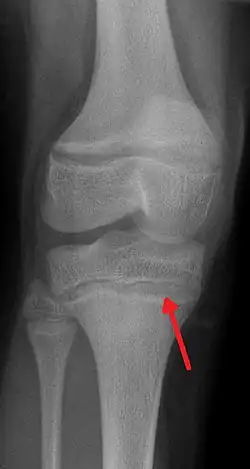

Ołowica, saturnizm[1] – zatrucie ołowiem powodujące osłabienie, bezsenność, brak łaknienia, zaburzenia widzenia i uszkodzenia wewnętrznych narządów ciała (wątroby oraz nerek). Dodatkowo poprzez wiązanie się z niektórymi enzymami mogą uszkadzać krwinki czerwone, a także komórki układu nerwowego. Substancją wiążącą ołów (Pb) w organizmie jest chelaton, dlatego też stosuje się go w leczeniu ołowicy.